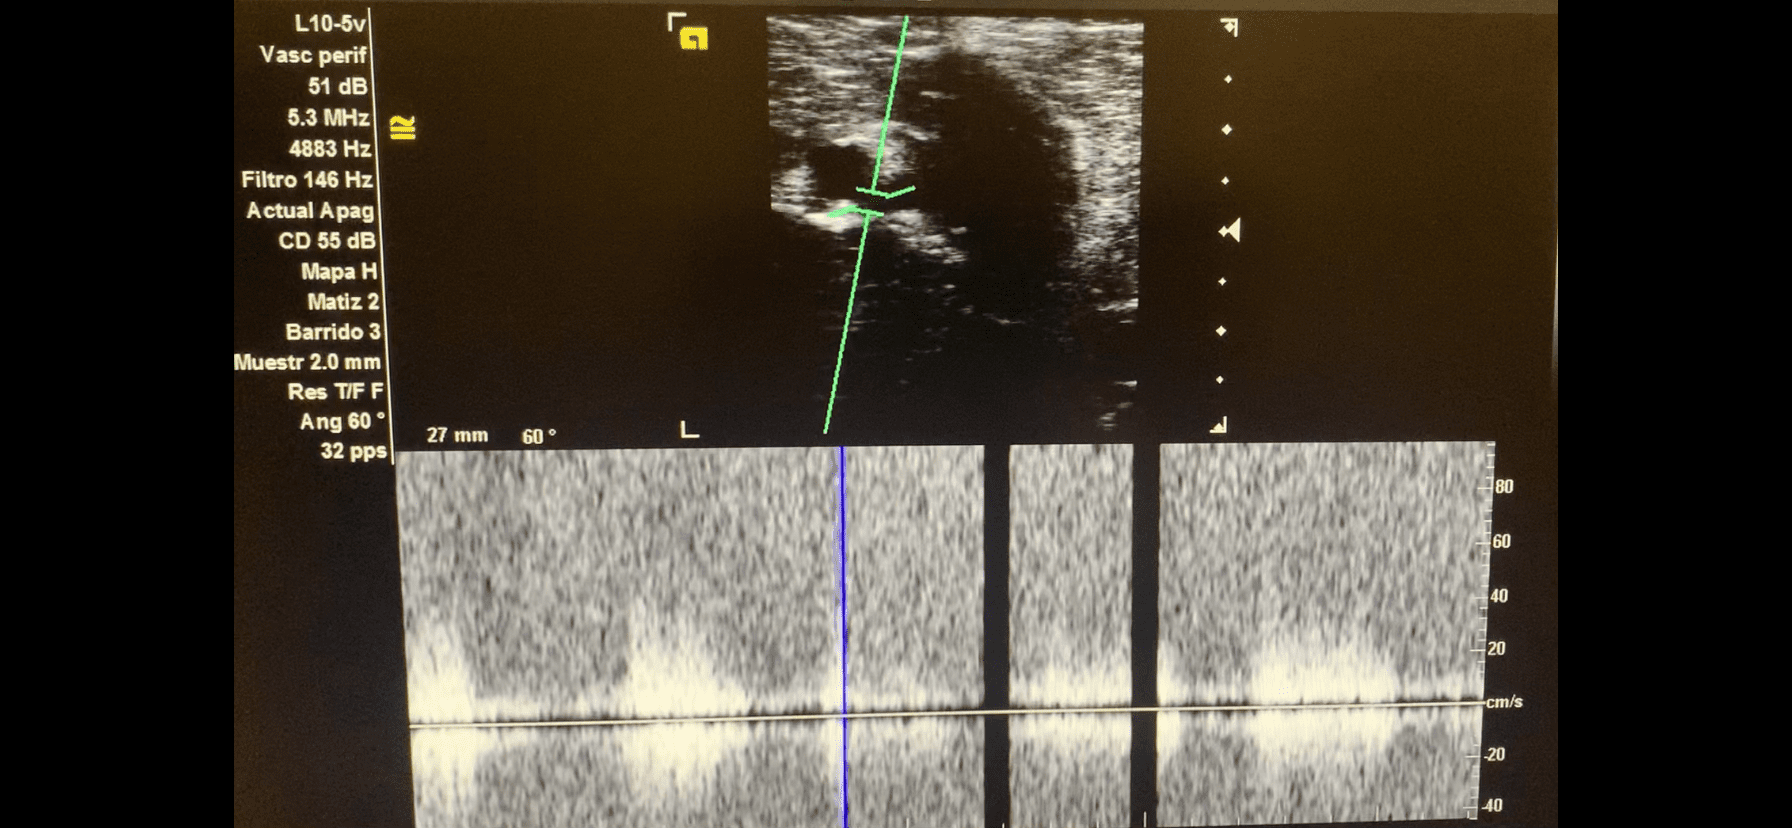

Imagen 3. Tono pulsátil de la fistula arteriovenosa.

AngioTC miembro inferior derecho: arterias femoral común, profunda y superficial permeables, de calibre normal, sin estenosis. Gran fístula arterio-venosa en tercio medio de femoral superficial, de alto flujo.

Gran fístula arteriovenosa de alto flujo en tercio medio de femoral superficial de miembro inferior derecho.